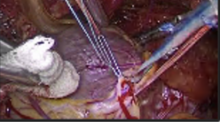

Obesity is often considered as a contraindication to minimally invasive coronary artery bypass grafting. Our concept has been that all incoming patients for isolated surgical coronary revascularization are eligible for a coronary artery bypass grafting through the left anterior minithoracotomy. For this purpose TCRAT procedure (Total Coronary Revascularization via Left Anterior Thoracotomy) was developed. The purpose of this study was to examine the outcomes of routine use of aforementioned surgical procedure in obese patients and determine if this approach is warranted.

We retrospectively reviewed 349 consecutive multivessel minimally invasive coronary grafting procedures done at our institution between July 2017 and January 2020, which represents the 98% of all patients who underwent isolated CABG in the same time frame. The outcomes of those who had obesity, defined as patients with a body mass index of greater than 30 kg/m2 were compared with non-obese patients. These groups were compared for differences in operative variables including cross clamp and cardiopulmonary bypass times as well as postoperative outcomes which included intubation times as well as ICU and hospital LOS. Postoperative complications including bleeding (return to OR) and infection (surgical wound) were also collected.

Our results would suggest that minimally invasive coronary grafting with TCRAT technique could be routinely applied in obese patients with results that are not clinically different from non-obese patients.